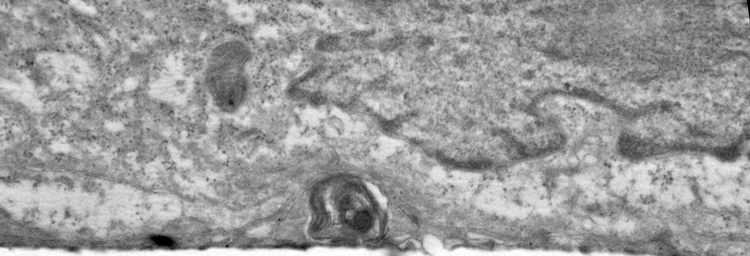

Electron micoscopy (top) and Confocal microscopy (below) analyses of patient-derived hiPSC-RPE demonstrate presence of sub-RPE drusen-like deposits (the central hallmark of SFD and similar maculopathies) that contain major constituents of drusen (APOE: red, TIMP3, green) in the human eye. Galloway et al PNAS 2017